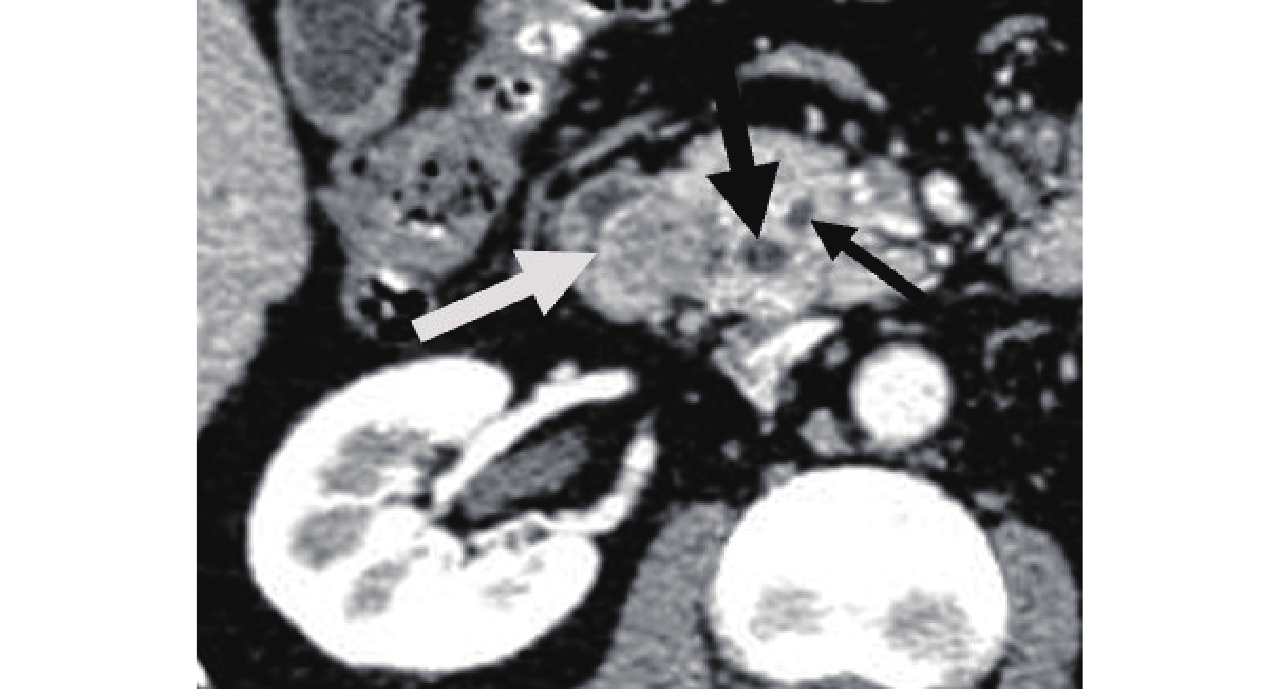

![]() 图 2 CPR显示正常壶腹部,胆总管(粗黑箭头)与主胰管(细黑箭头)汇合成肝胰壶腹(细白箭头),突入十二指肠降段下1/3内侧壁,形成十二指肠大乳头(粗白箭头)Figure 2. CPR shows the normal ampulla, the common bile duct (thick black arrow) and the main pancreatic duct (thin black arrow) converging to form Vater's ampulla (thin white arrow), which protrudes into the medial wall of the lower 1/3 of the descending duodenum to form duodenal papilla (thick white arrow)

图 2 CPR显示正常壶腹部,胆总管(粗黑箭头)与主胰管(细黑箭头)汇合成肝胰壶腹(细白箭头),突入十二指肠降段下1/3内侧壁,形成十二指肠大乳头(粗白箭头)Figure 2. CPR shows the normal ampulla, the common bile duct (thick black arrow) and the main pancreatic duct (thin black arrow) converging to form Vater's ampulla (thin white arrow), which protrudes into the medial wall of the lower 1/3 of the descending duodenum to form duodenal papilla (thick white arrow)2.2 十二指肠乳头癌影像表现

图 2 CPR显示正常壶腹部,胆总管(粗黑箭头)与主胰管(细黑箭头)汇合成肝胰壶腹(细白箭头),突入十二指肠降段下1/3内侧壁,形成十二指肠大乳头(粗白箭头)

Figure 2. CPR shows the normal ampulla, the common bile duct (thick black arrow) and the main pancreatic duct (thin black arrow) converging to form Vater's ampulla (thin white arrow), which protrudes into the medial wall of the lower 1/3 of the descending duodenum to form duodenal papilla (thick white arrow)